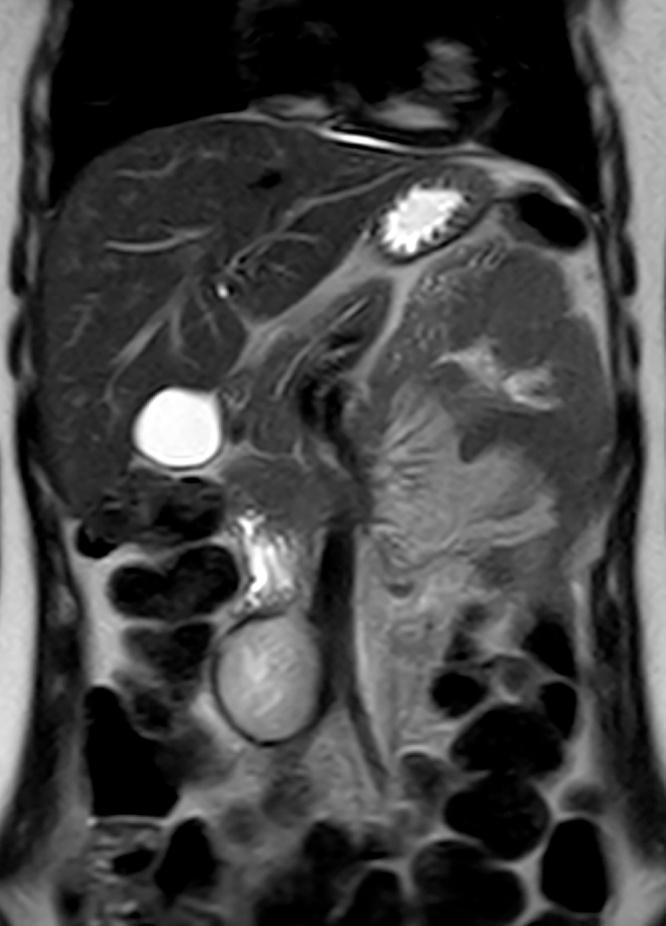

We will present a 17-year-old woman with a retroperitoneal tumour in contact with the aorta and the inferior vena cava, treated with embolization prior to the surgical resection via laparotomy.

我们将介绍一名17岁女性,其患有与主动脉和下腔静脉相邻的腹膜后肿瘤,在经剖腹手术切除前接受了栓塞治疗。